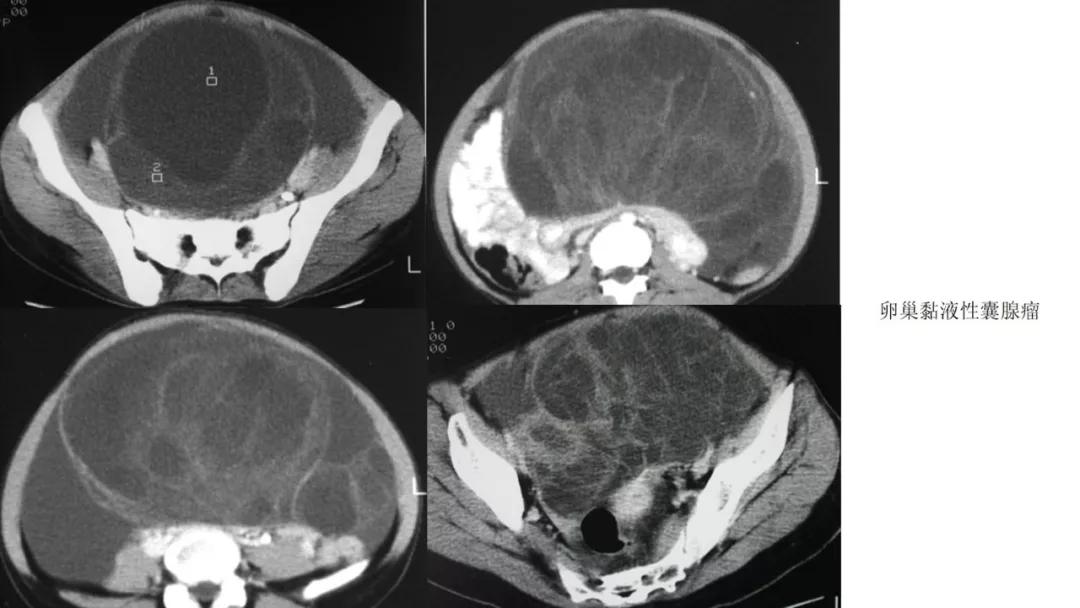

上皮性肿瘤:最常见,恶性多(卵巢癌),良性少。好发于50Y以上,发现时多为中晚期。多呈囊性或以囊性为主的囊实性肿块,完全实性者少见。形态多数不规则,边界模糊,囊壁及房间隔常不规则增厚,菜花样肿物或壁结节,囊实性区域分界不清,实性肿瘤常有不规则低密度或坏死区,可有边界模糊沙粒状或块状钙化,中-高度强化。良性者边界清晰,囊壁薄光整,无壁结节,实性部分呈无或轻度强化。

- 卵巢的黏液性肿瘤破裂,上皮和黏液会种植在腹膜引起胶冻样的腹膜假黏液瘤,这一点跟阑尾的黏液性肿瘤类似,都是腹膜假黏液瘤的病因。